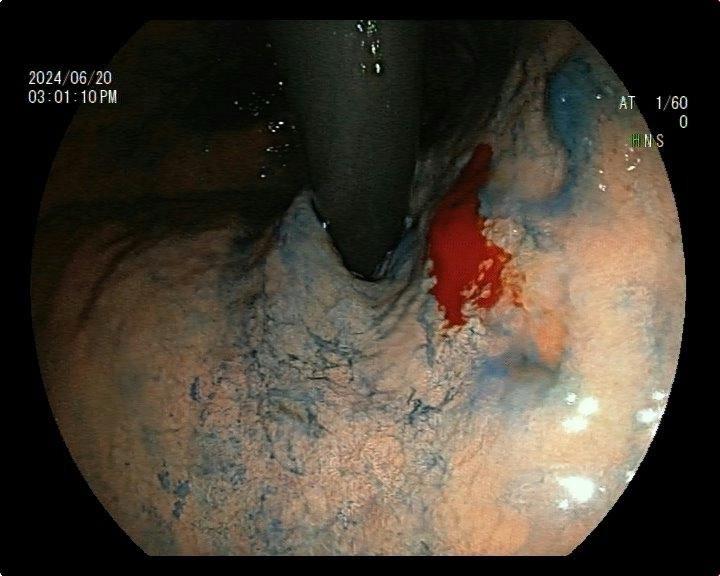

男,60岁,慢性萎缩性胃炎复查。慢性萎缩性胃炎多年,本次复查:贲门下,1.0cm左右,色调微黄,见自发性出血点,LCI可见“紫包橙”,BLI局部茶色,胃小区结构紊乱,活检提示增生活跃伴不典型,随访? D?